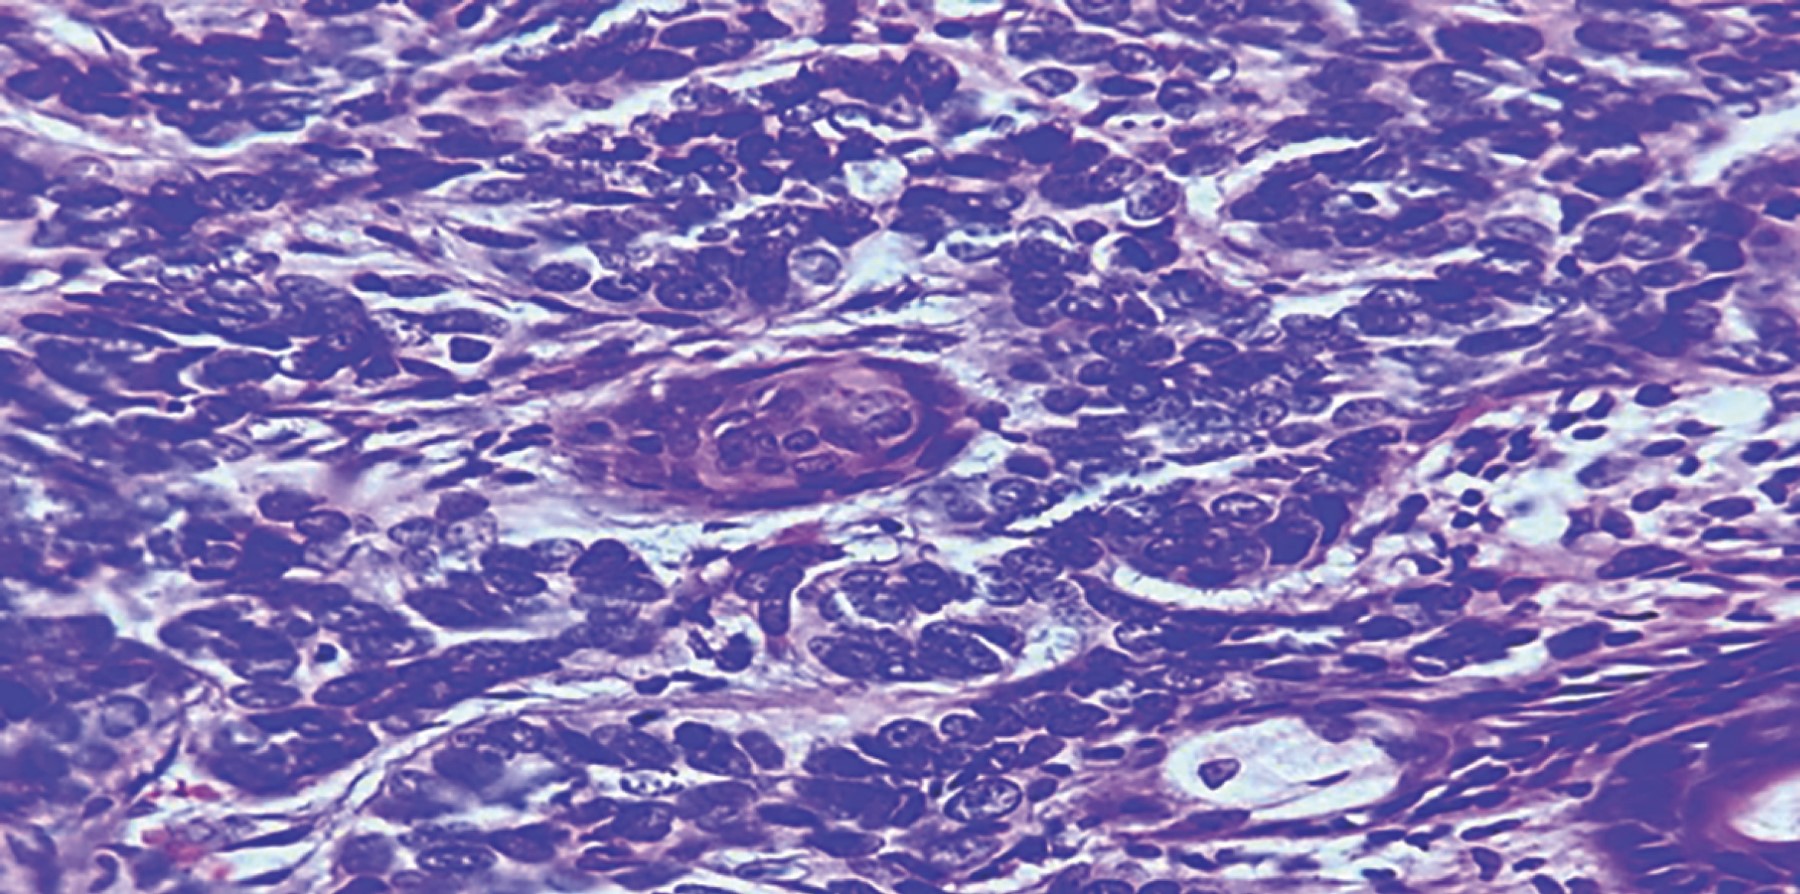

Hombre de 60 años con antecedente de diabetes mellitus tipo II, hipertensión arterial sistémica, insuficiencia cardiaca crónica y consumo crónico de alcohol, cocaína y tabaco. Acudió a nuestra unidad hospitalaria por medio de la consulta externa de primera vez al servicio de cirugía plástica y reconstructiva por tumoración ulcerativa en labio superior derecho de cinco años de evolución. A la exploración física se encontraron los siguientes hallazgos: tumoración de 3 × 2 cm en el labio superior derecho, con ulceración y costra, el resto de la exploración normal. Se inició protocolo quirúrgico con plan de resección de la tumoración más colgajo de avance. Al contar con protocolo quirúrgico completo, se programó para cirugía electiva, ingresó por medio de cirugía ambulatoria y se inició el procedimiento quirúrgico previa asepsia y antisepsia; se procedió a realizar marcaje de la lesión (Figura 1), con resección de la tumoración con márgenes de 5 mm sobre el labio y ala nasal derecha; se disecó por planos resección de ala izquierda para compensar márgenes de lesión (Figura 2). Se liberó el pedículo de tejido subcutáneo elástico de sus uniones adiposas medial y lateral con la grasa circundante de la mejilla, al tiempo que se preservaba su suministro vascular derivado de sus uniones profundas. La isla cutánea se dirigió hacia el defecto mediante la colocación de un gancho cutáneo en su borde anterior. Se realizó avance de colgajo sobre pedículo de tejido subcutáneo; se efectuó cierre con Vicryl 5-0 y Nylon 5-0, se colocó gasa estéril y se dio por terminado el procedimiento quirúrgico (Figura 3). Se egresó al paciente y se citó a consulta externa con recomendaciones generales. Se valoró una semana después de la cirugía con evolución favorable. Se retiraron puntos de sutura y se recabó el reporte de histopatología (Figura 4) de carcinoma basocelular metatípico (basoescamoso), con profundidad de la invasión 2.5 mm, nivel anatómico Clark IV, sin invasión linfovascular ni perineural y sin afectación de márgenes periféricos. Se dio seguimiento a un mes del postquirúrgico (Figura 5) y a tres meses (Figura 6), con buena evolución estético-funcional.

Figura 4